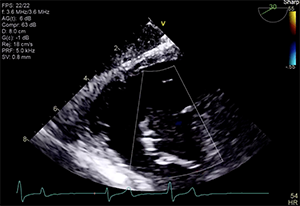

The patient’s left ventricular (LV) systolic function was mildly reduced (LV ejection fraction, 40%–45%), and he had a dilated right ventricle with mild systolic dysfunction based on standard normal ranges (Figure 1 and Figure 2). His right ventricular (RV) systolic pressure was estimated to be 56 mm Hg, as assessed by echocardiography. The results of right heart catheterization showed a pulmonary capillary wedge pressure of 19 mm Hg (V wave to 28 mm Hg), pulmonary artery pressure of 50/14 mm Hg (mean, 29 mm Hg), RV pressure of 50/14 mm Hg, and right atrial pressure of 15 mm Hg (V wave to 20 mm Hg).

Transthoracic and transesophageal echocardiography (TEE) confirmed severe functional TR due to annular dilation associated with RV and right atrial enlargement. Mild leaflet tethering, predominantly septal, was also appreciated. The coaptation gap was < 10 mm and the jet origin was predominantly central with extension toward the anteroseptal commissure. Image quality in both transesophageal midesophageal and transgastric windows were good (Videos 1–5).

Dr. Hahn: The imaging for all transcatheter devices drives procedural success and these case images are very good. However, once the delivery catheters enter the right atrium, acoustic shadowing (the severity of which cannot be easily determined preprocedurally) is often present, and interventional imaging specialists must be flexible in their imaging protocol and be able to quickly adjust to imaging challenges.

Dr. Fam: Given the presence of both mechanical mitral and aortic valve replacements, shadowing of the tricuspid valve might be an issue during the procedure, which might make TEE visualization of leaflet grasping challenging. This usually can be overcome by experienced echocardiographers with adjunctive use of TTE and intracardiac echocardiography as needed.

An edge-to-edge device was selected due to the acceptable coaptation gap and expected good-quality procedural imaging for guidance. A single Pascal device was deployed between the anterior and septal leaflets to successfully repair this patient’s tricuspid valve. Postprocedure TR was mild to moderate, from a baseline of severe (or likely “massive” if using an expanded grading scheme). Independent leaflet grasping was utilized due to the mild relative tethering of the septal leaflet, which allowed optimization of leaflet insertion to ensure maximal effect and stability of the single device. There were no procedure-related complications.